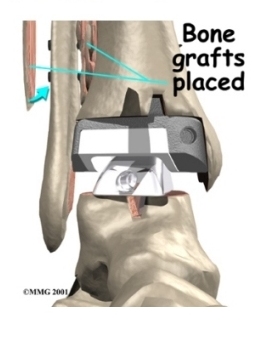

X-rays will be taken several times after your surgery to make sure that the artificial joint has not moved out of place and that the fusion between the fibula and the tibia is forming. When the uncemented type of implant is used, X-rays also help determine whether bone is attaching to the metal implant.